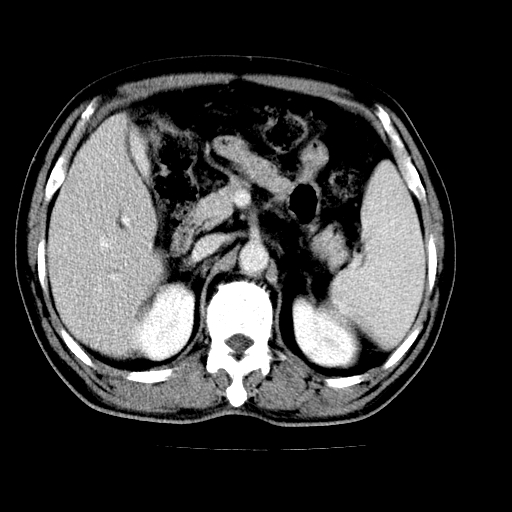

男,66岁,上腹部不适、黄染一周。彩超示:肝左叶占位,肝内胆管扩张,胆总管扩张,胆总管占位?

肝左叶不规则软组织肿块影,边缘不规整邻近肝实质受累分界不清;肝内胆管(左叶)明显扩张成“软藤状”,诊断:肝左叶胆管细胞癌。

肝左叶占位性病变,并胆管扩张,符合胆管细胞癌ct表现,门脉左支受累,左肾囊肿。窗宽太窄了,其他的看不清

左叶胆管细胞癌累及胆总管,门脉左支受侵,慢性胆囊炎胆结石,左肾小囊肿

胆囊缩小,其内胆汁浓缩,也提示梗阻部位应该位于胆囊管起始部以上或是胆囊管受累及,支持肝外胆管癌。